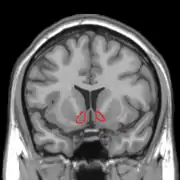

![]() Коронарна проекція |

| Прилегле ядро на МРТ мозку людини (позачене червоним) |